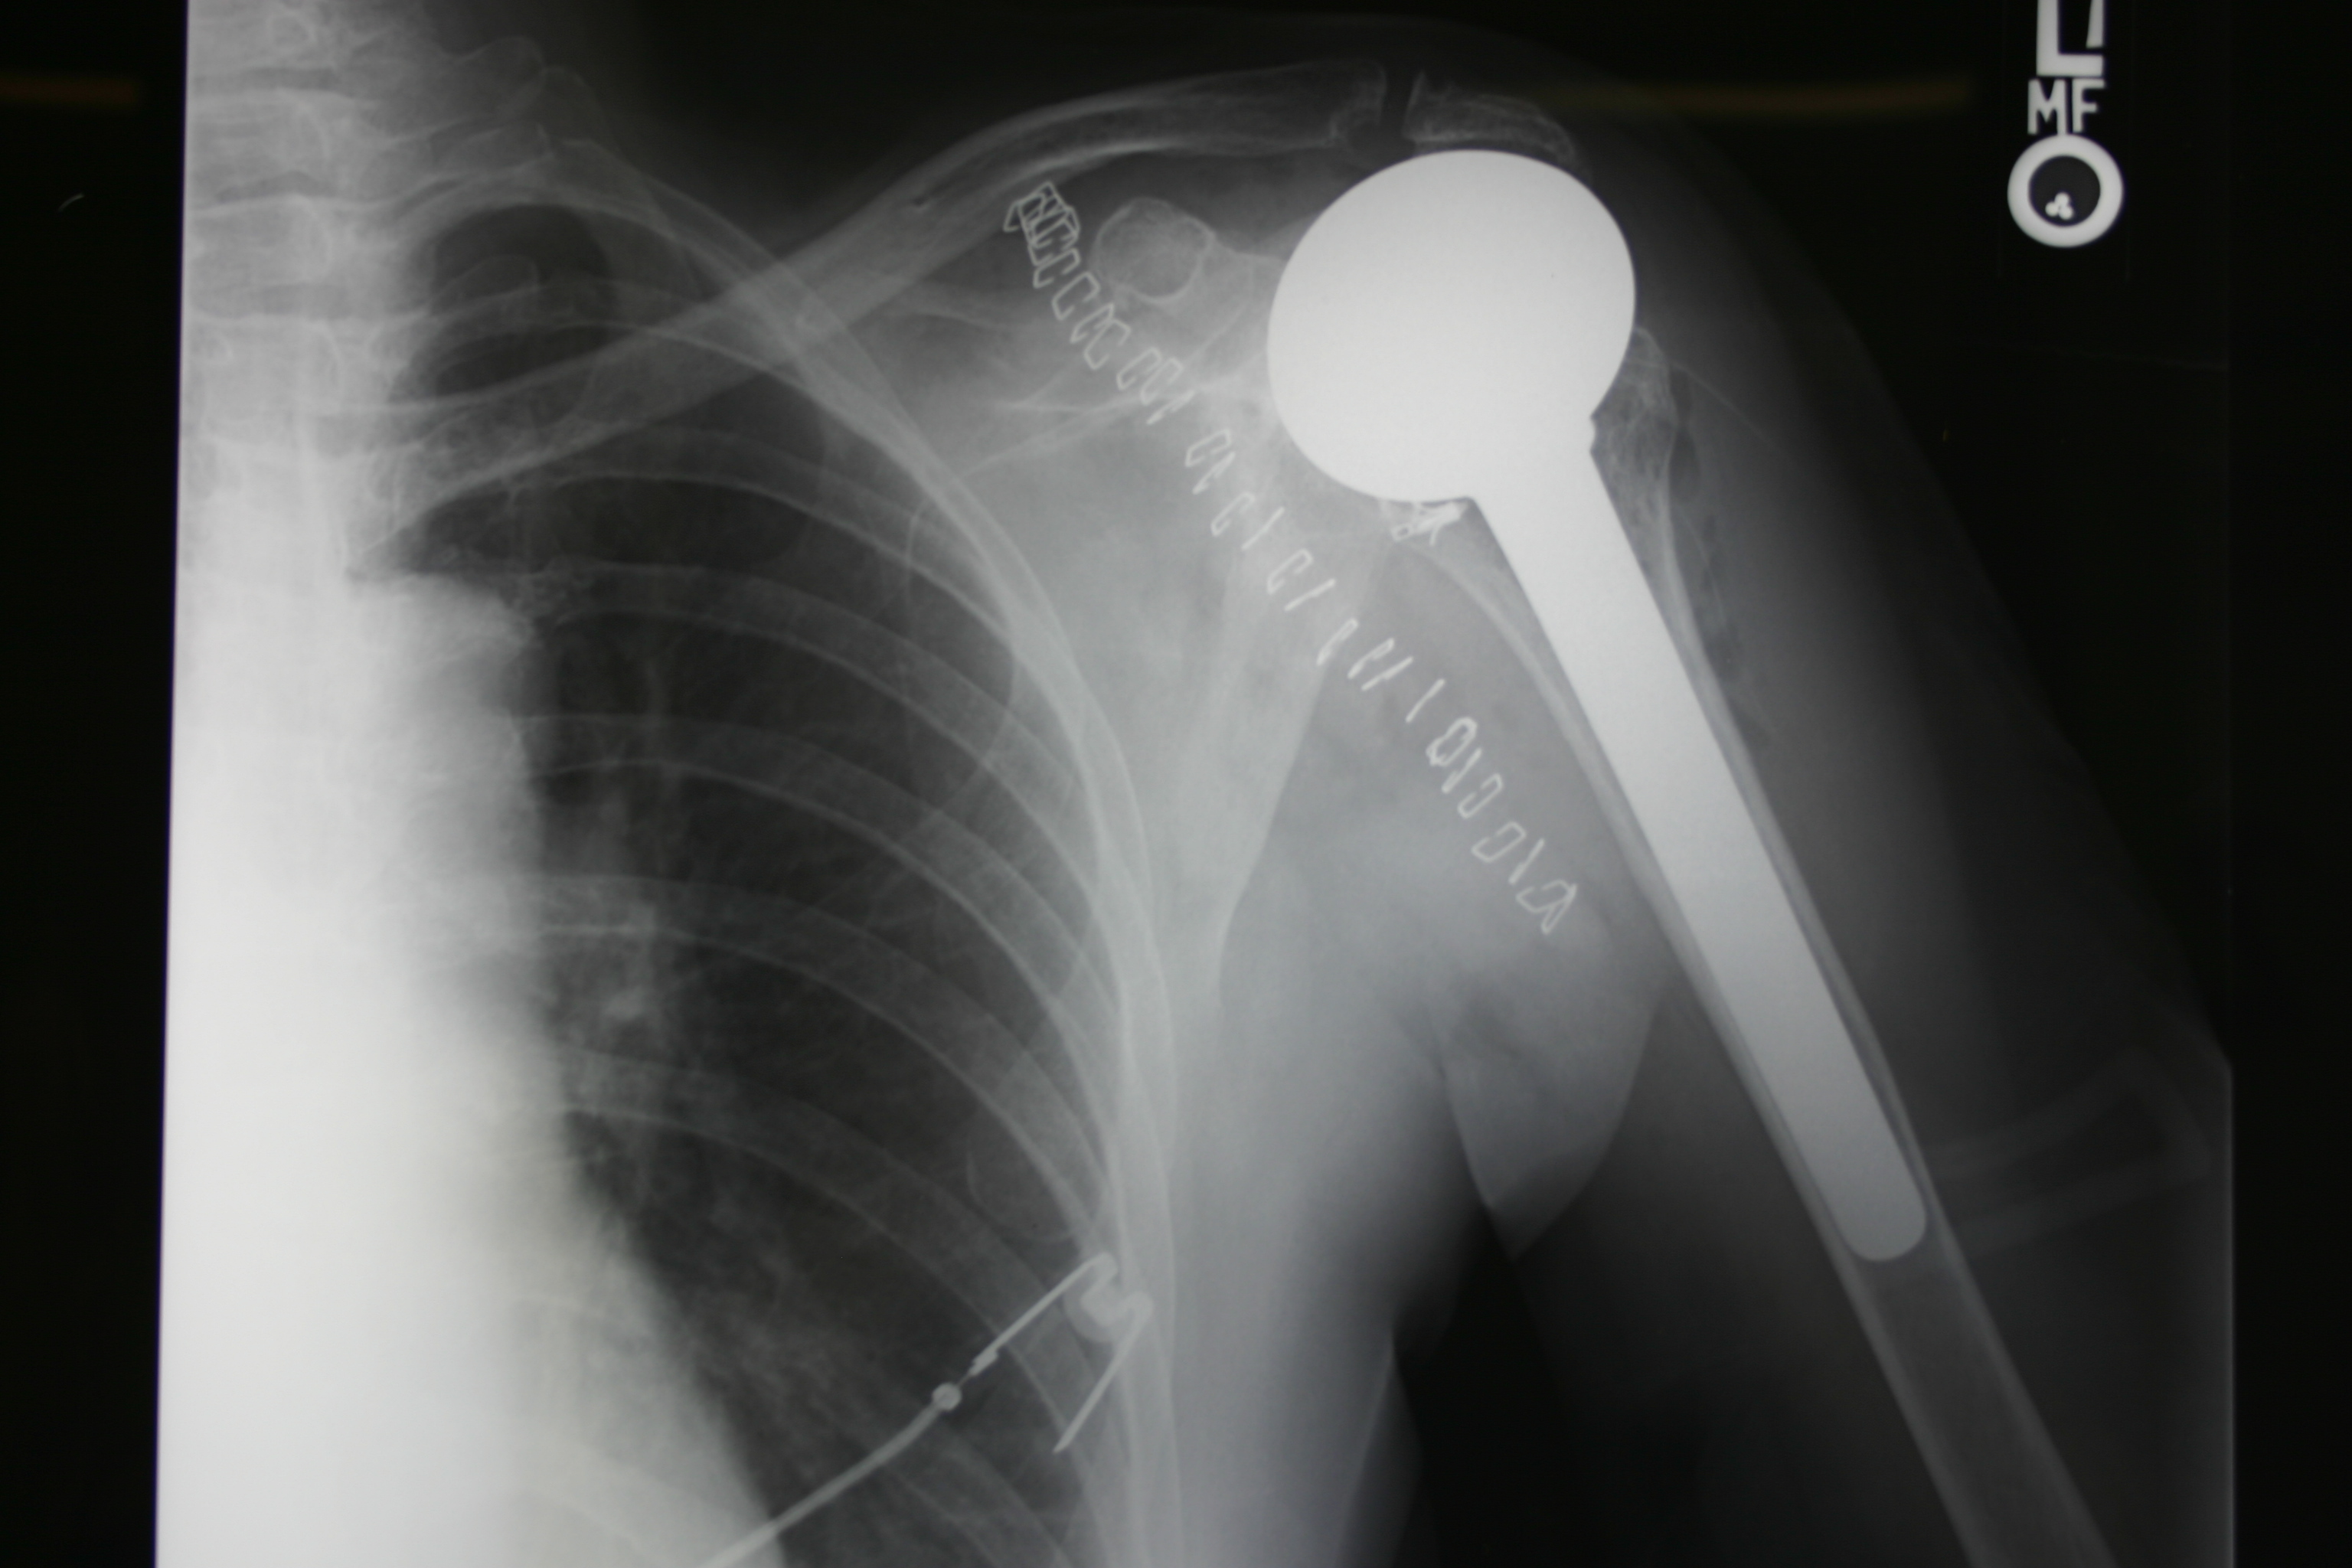

Zimmer Biomet Shoulder Replacement

Los Angeles Robotic Shoulder Replacement Surgery Beverly Hills Joint What Is Shoulder Replacement Surgery Called in shoulder replacement surgery, the damaged parts of the shoulder are removed and replaced with artificial components (parts), called a prosthesis. Replacement of just the head of the humerus bone (ball) replacement of both the ball and the socket (glenoid) cause. Total shoulder replacement, also known as total shoulder arthroplasty, is the removal of portions of the shoulder joint,. What Is Shoulder Replacement Surgery Called.

Reverse Shoulder Arthroplasty — What Is Shoulder Replacement Surgery Called The treatment options are either: Total shoulder replacement, also known as total shoulder arthroplasty, is the removal of portions of the shoulder joint, which are. what is shoulder replacement surgery? are you scheduled to have shoulder replacement surgery? shoulder replacement surgery involves removing damaged parts of the shoulder bones and replacing them with. A shoulder replacement removes. What Is Shoulder Replacement Surgery Called.

Zimmer Biomet Shoulder Replacement What Is Shoulder Replacement Surgery Called Replacement of just the head of the humerus bone (ball) replacement of both the ball and the socket (glenoid) cause. The treatment options are either: Learn more about the procedure, risks, recovery time,. a shoulder replacement is a procedure that tries to eliminate the source of pain and dysfunction by replacing damaged parts of the shoulder joint with artificial.. What Is Shoulder Replacement Surgery Called.